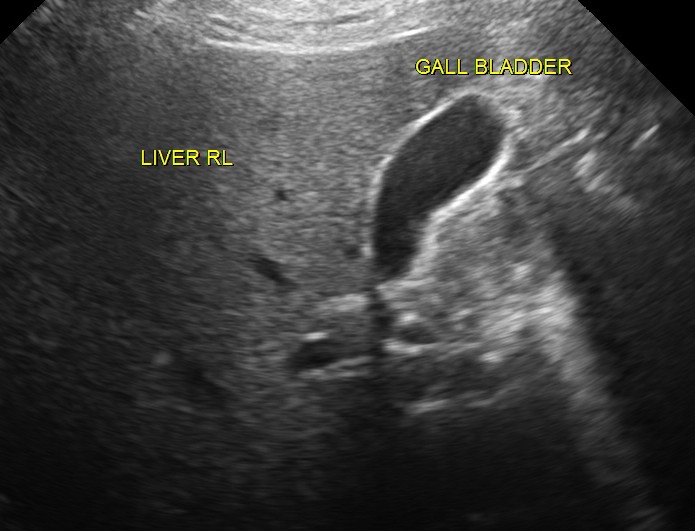

Ultrasound revealed normal liver, gall bladder, pancreas, spleen ,post menopausal shrunk uterus and normal right kidney.